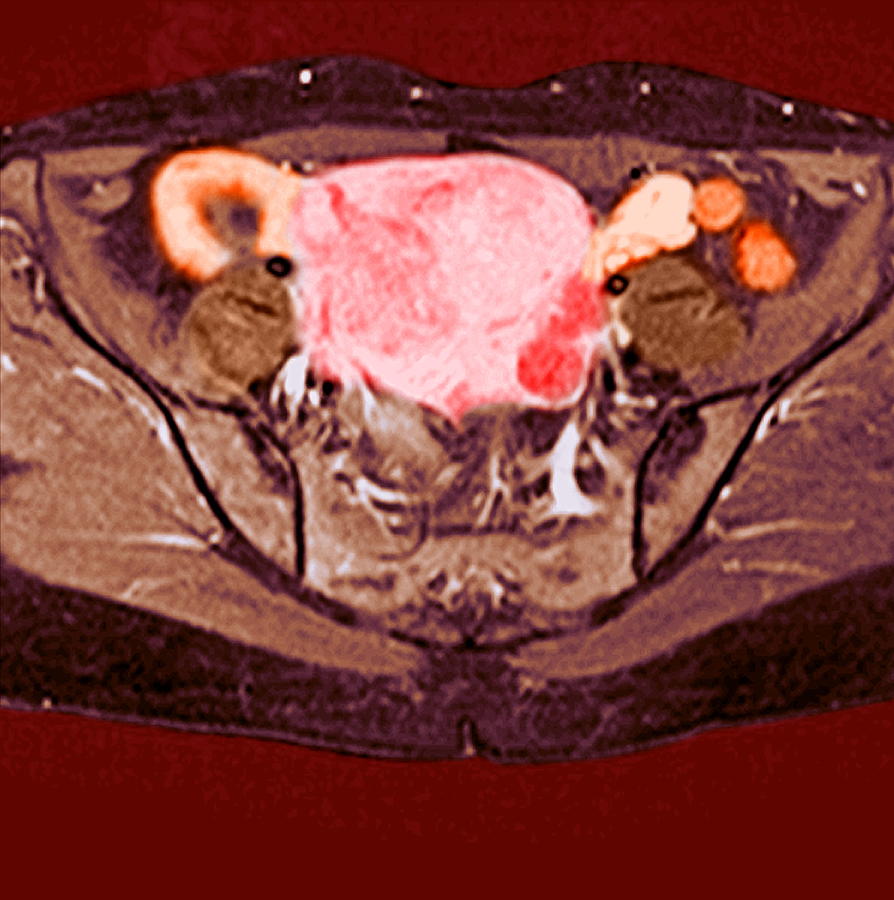

MRI pelvis of a large posterior wall fibroid with cystic degeneration …

Detecting fibroids with imaging – medical empowerment

Uterine Fibroid, Mri Scan Photograph by Du Cane Medical Imaging Ltd

Pelvic MRI for Fibroids – Why You Need an MRI to Detect Fibroids

Additional pathologies found during uterine fibroid MRI screening. a …

Fibroids UFE | Body MRI

Uterine Fibroid, Mri Scan Photograph by Du Cane Medical Imaging Ltd